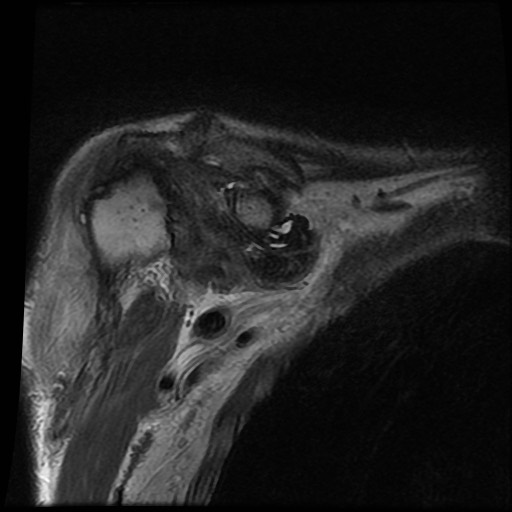

Hình ảnh MRI:

Tràn dịch lan tỏa tất cả các khớp cổ tay.

Phù tủy xương lan tỏa tất cả các xương cổ tay.

Bào mòn xương, ví dụ tại xương thuyền, xương đầu và xương móc.

Phá hủy khe khớp và sụn khớp, rõ nhất tại khớp STT và CMC4/5.